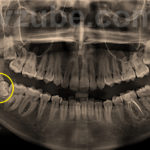

- Высокий риск развития кариеса. Зубы мудрости вырастаю на стыке двух челюстей — верхней и нижней. Такое расположение третьих моляров делает их практически недосягаемыми для качественной чистки щеткой и нитью. В определенной мере ситуацию спасает использование ирригатора, но даже в этом случае вероятность развития кариеса на зубах мудрости очень велика. Кроме этого, в силу особенностей своего строения, восьмерки с трудом поддаются лечению, и его эффект редко сохраняется надолго.

- Угроза для мягких тканей полости рта и состояния здоровья в целом. Причина этого — крайне часто возникающие ситуации, при которых зуб мудрости прорезывается частично, или изначально растет в сторону. В первом случае моляр, взрезав десну, продолжает «сидеть» в ней, не проявляя признаков активного роста. Но образовавшийся в десне карман становится «ловушкой» для мягкого налета и фрагментов пищи, которые, скапливаясь в нем, создают питательную среду для болезнетворных микроорганизмов. Это, в свою очередь, приводит к развитию гнилостных процессов с выделением токсинов, которые вместе со слюной попадают в горло и желудок, повышая вероятность заболеваний. Но пока зуб мудрости, даже не прорезавшийся, будет находиться на своем месте, десневой карман не может эпителизироваться и зажить — для этого необходимо удаление зуба.

При росте третьего моляра в сторону, опасности подвергаются мягкие ткани. Постоянное травмирование слизистой оболочки щеки и десны может привести к озлокачествлению клеток и развитию онкологического процесса. - Необходимость ортодонтического лечения. Коррекция прикуса и выравнивание зубного ряда всегда предусматривают предварительное лечение уже существующих заболеваний зубов и десен, и их профилактику на весь период ношения брекет-систем В этом случае, если «восьмерка» расположена слишком тесно к соседнему зубу и вызывает скученность зубов (одну из наиболее распространенных причин заболеваний зубов и десен), ее следует удалить. Кроме того, присутствие полупрорезавшегося зуба может снижать эффективность ортодонтического лечения, поэтому перед установкой брекетов его также рекомендуется удалить.